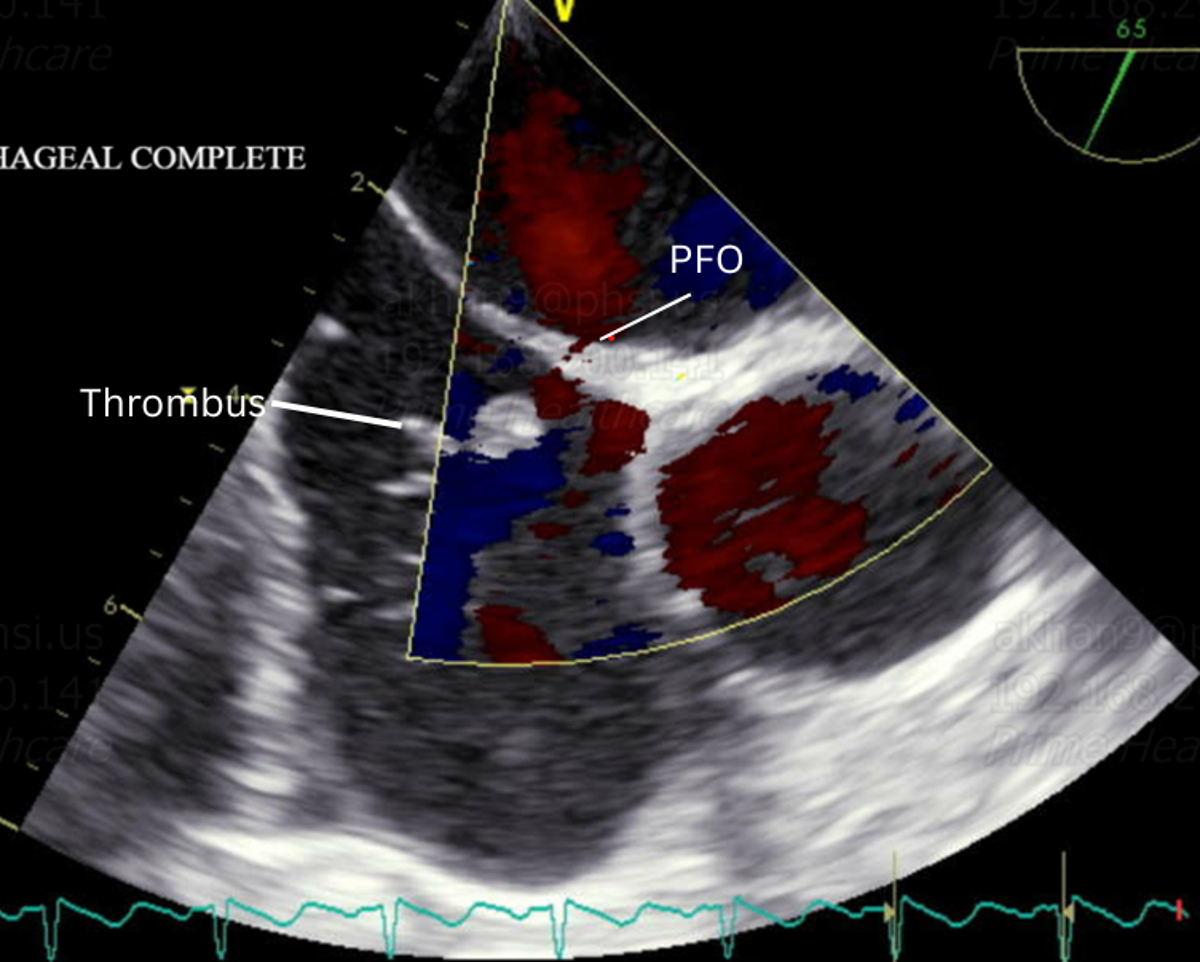

At follow-up, she remained emotionally distressed and convinced she had suffered a stroke. Repeat TTE raised concern for an intracardiac mass. A transesophageal echocardiogram (TEE) revealed a port-a-catheter tip in the right atrium with a large, mobile thrombus attached to its distal end. A small PFO with intermittent right-to-left shunting was also identified. The thrombus moved like a pendulum, intermittently striking the interatrial septum at the PFO. It is likely that embolization of a portion of the thrombus through the PFO led to a TIA. Interventional Radiology administered catheter-directed tPA to facilitate clot dissolution.

This case highlights a rare but clinically significant mechanism of paradoxical embolism originating from a central venous catheter, diagnosed through high clinical suspicion and confirmatory imaging.

In patients with neurologic symptoms and indwelling catheters, paradoxical embolism should be considered. TEE plays a vital role in detecting thrombi and intracardiac shunts. Early recognition and targeted therapy may prevent recurrence of embolic events.